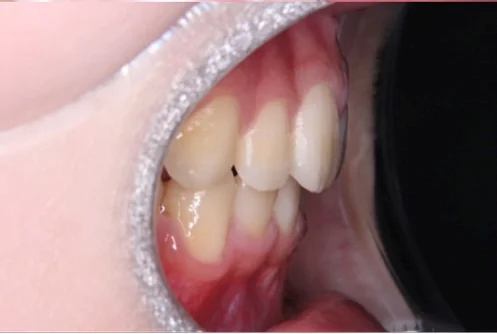

治療後

| 相談内容(主訴) | 出っ歯が気になる |

|---|---|

| 診断結果/行った治療内容 | 上顎前突/インビザライン矯正 |

| 治療期間/回数 | 1.5年/18回 |

| 治療費用 | 80万円 |

| 治療のリスク/副作用 | 歯の移動に伴い歯肉退縮を起こすことがあります/顎関節に症状が出ることがあります |